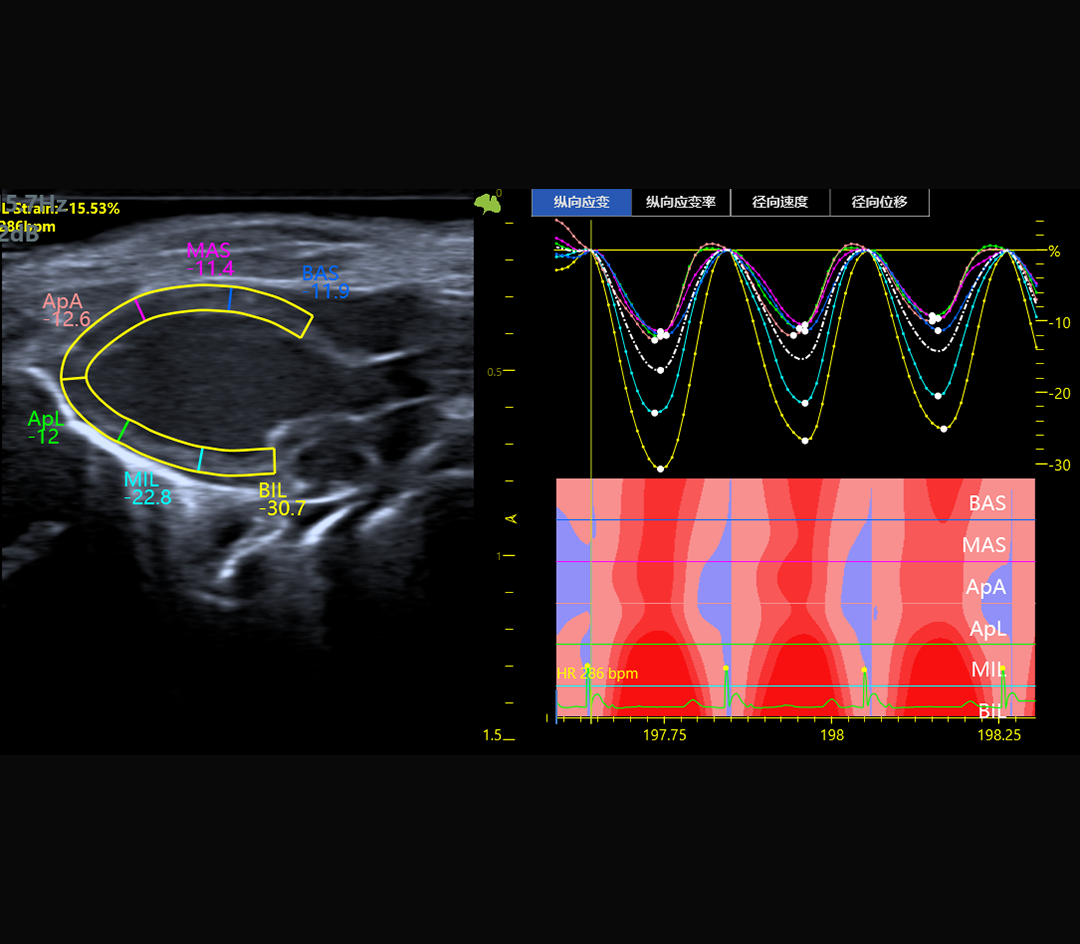

Analyse du strain myocardique

Le V6 LAB intègre des algorithmes dédiés au traitement massif des données RF :

Imagerie B-mode haute résolution

M-mode précis pour l’analyse fonctionnelle cardiaque

Résultat : une imagerie fine, stable et quantitative, adaptée à l’étude de la fonction cardiovasculaire, du flux sanguin et des structures tissulaires complexes.